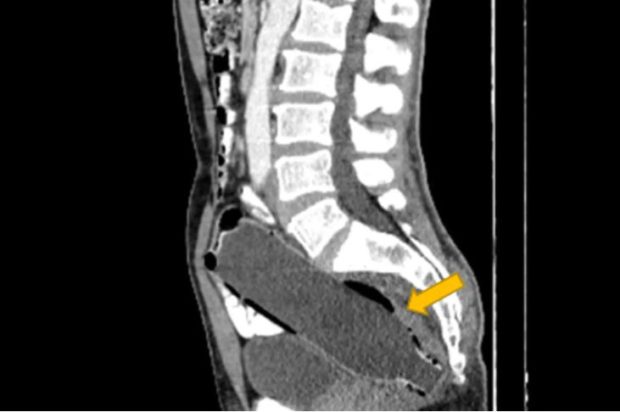

Ο άνδρας συνέχισε να κρύβει με επιτυχία το οδυνηρό μυστικό του, μέχρι που αποκαλύφθηκε στους γιατρούς μέσω αξονικής τομογραφίας.

Σύμφωνα με ένα άρθρο στο Clinical Case Reports Journal, ο άνδρας απέφυγε να αναφέρει ότι είχε τοποθετήσει το αντικείμενο μόνος του, λόγω «αμηχανίας» και «φόβου για τη γυναίκα του».